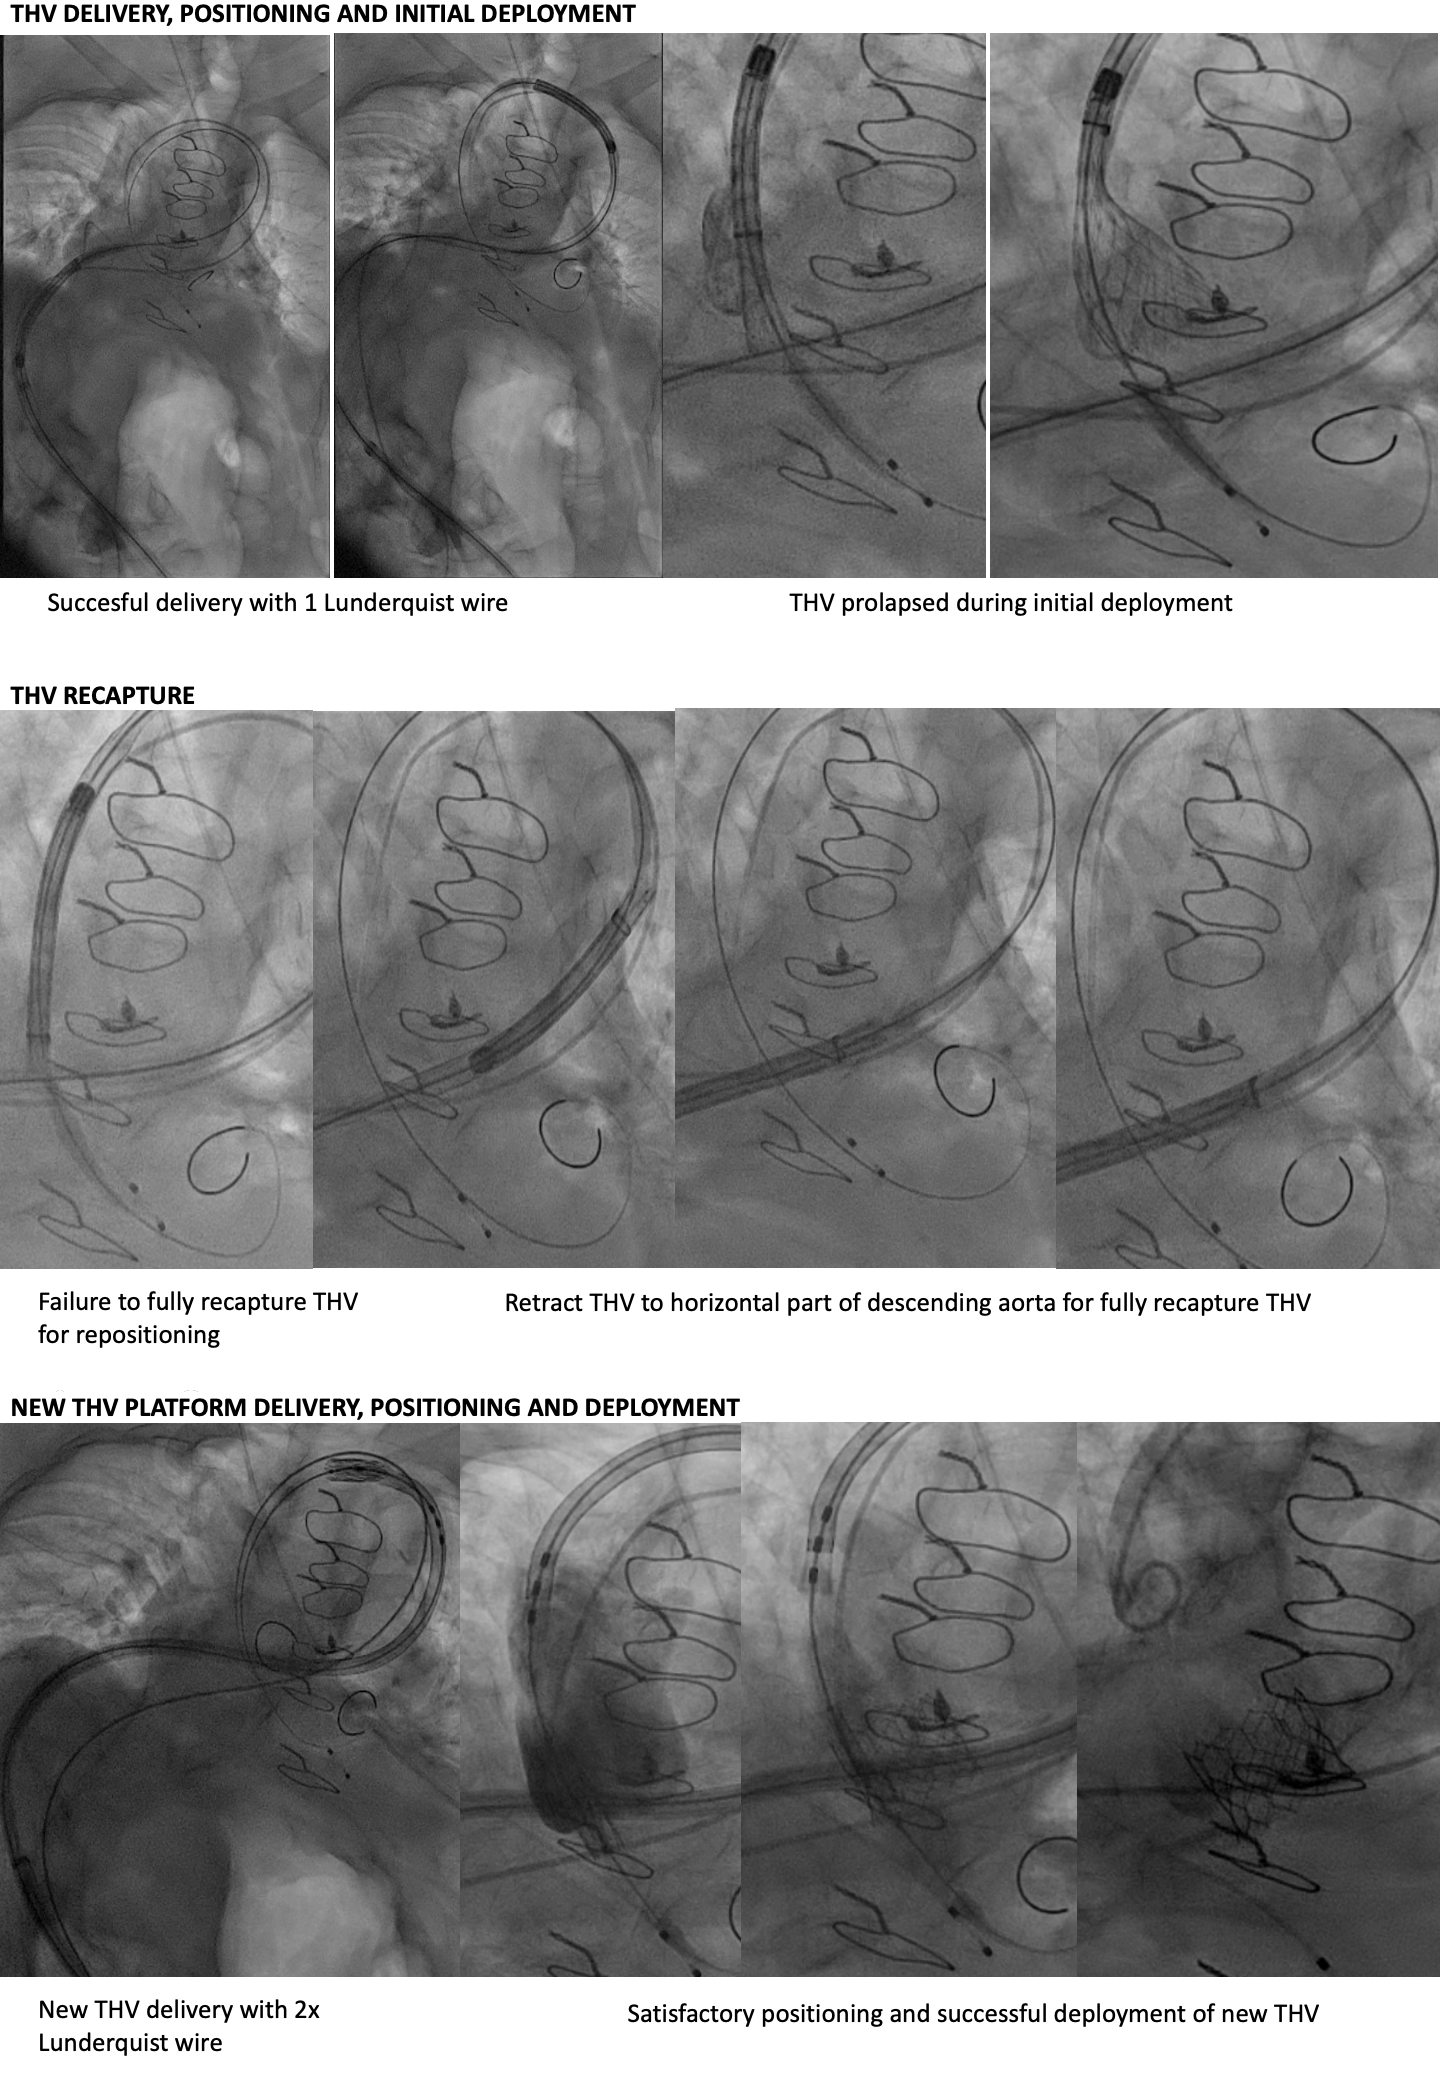

She was turned down for surgical AVR (STS 6.2%, EuroScoreII 8.0%, resternotomy, high BMI, short stature, kyphoscoliosis, COPD and breast cancer history) during Heart Team discussion. For TAVI risk, she is a young lady with almost type 0 bicuspid aortic stenosis and severely calcified raphe, tortuous aorta and left subclavian artery. We had discussed multiple strategy and decided for left transfemoral TAVI using Evolut FX 29mm. After 18mm balloon valve predilation, we successfully delivered THV to aortic root with 1 Lunderquist wire on first attempt. After satisfactory positioning, the THV had prolapsed during initial deployment. We were unable to recapture the THV nose cone tip for repositioning despite multiple maneuvers. We managed to realign the nose cone tip and fully recapture the THV by retracting to straighter part of descending aorta.This time, we had to use 2 Lunderquist wire to redeliver THV across the aortic arch. This maneuver was repeated 3 times as the THV would not remain in place due to the complex calcified nature of bicuspid valve and severe aorta tortuosity. We decided to switch to plan B using a new THV platform - Sapien 3 Ultra Resilia 23mm+1. We exchanged to E-Sheath 14Fr and successfully deliver new THV around the curves using 2 Lunderquist buddy wire. After satisfactory positioning, we successfully deployed the new THV under rapid pacing with excellent angiographic and echocardiographic results. The patient was well and discharged at day 3 post TAVI.

Case Summary

Super-stiff buddy wire technique is very useful in tackling aortic tortuosity. Extensive complex calcified bicuspid aortic valve with severe aortic tortuosity can significantly impact on certain THV positioning, deployment and recapturability. There is a crucial strategic need to have plan B when pursuing TAVI procedure in patient with complex anatomy.